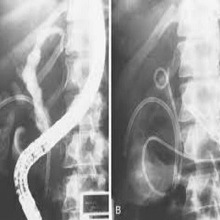

| Формирање калкулуса у мокраћном систему и морбидитет који он изазива данас поприма пандемијске размере и у константном је порасту. Калкулус се најчешће формира код особа који живе у земљама са топлом и сувом климом, а преваленција се креће између 2% и 20%. |

| У великом броју рандомизовано контролисаних и опсервационих студија обухваћених метаанализама утврђено је смањење ризика за појаву рецидивантних епизода калкулозе чак од 60% до 80% уколико је дошло до значајно повећаног уноса течности, и то првенствено воде. |